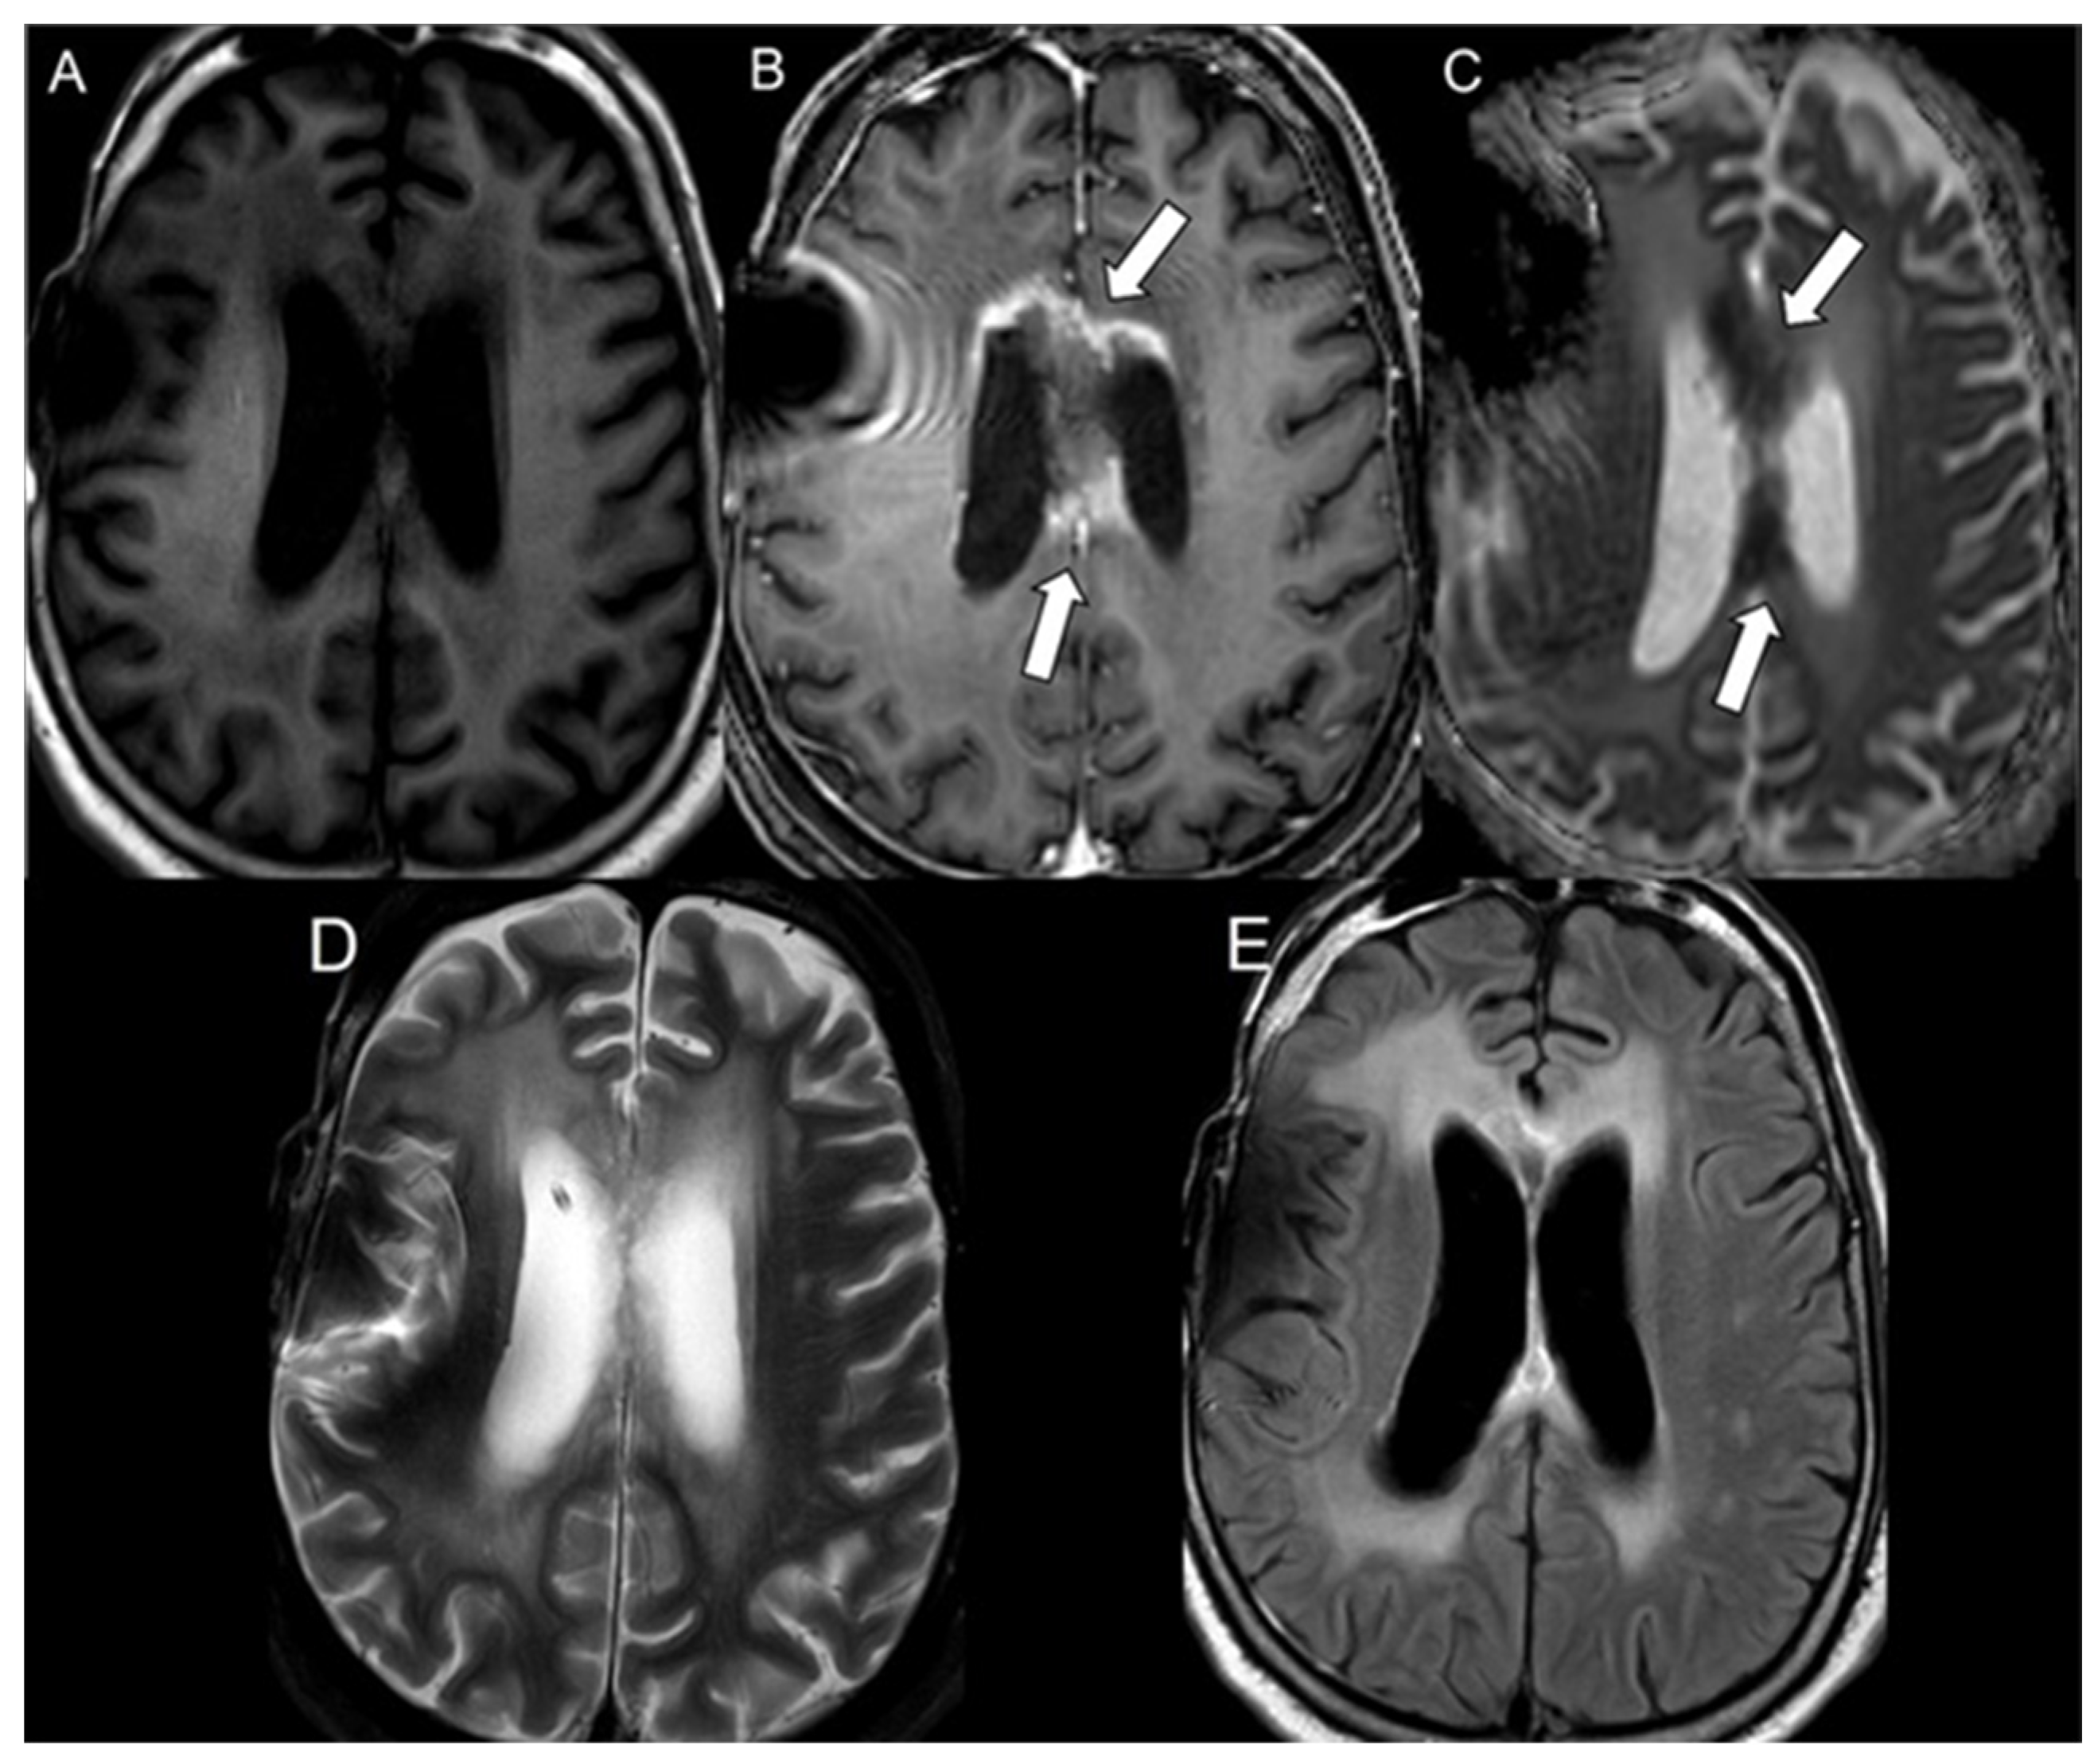

| 1 | Still alive | GBM | + | + | + | CC | N/A | 181 | N/A |

| 2 | 32 | GBM | + | + | + | CC | 90 | 74 | 16 |

| 3 | 45 | GBM | + | + | + | CC | 574 | 61 | 513 |

| 4 | 77 | GBM | + | + | + | CR | 424 | 58 | 366 |

| 5 | 57 | GBM | + | + | + | CC | 647 | 339 | 308 |

| 6 | Still alive | GBM | + | + | + | CC | N/A | 258 | N/A |

| 7 | 48 | GBM | + | + | + | PV | 283 | 16 | 267 |

| 8 | 68 | GBM | + | + | + | CR | 92 | 34 | 58 |

| 9 | 67 | GBM | + | + | + | CR | 573 | 150 | 423 |

| 10 | 64 | GBM | + | + | + | PV | 589 | 25 | 564 |

| 11 | 57 | GBM | + | + | + | CC | 281 | 57 | 224 |

| 12 | 67 | GBM | + | + | + | CC | 75 | 41 | 34 |

| 13 | 65 | GBM | + | + | + | PV | 272 | 90 | 182 |

| 14 | 48 | GBM | + | + | + | PV | 717 | 371 | 346 |

| 15 | 51 | GBM | + | + | + | CC | 229 | 41 | 188 |

| 16 | 72 | GBM | + | + | + | PV | 878 | 49 | 829 |

| 17 | 52 | GBM | + | + | + | CC | 575 | 140 | 435 |

| 18 | 54 | GBM | + | + | + | CC | 651 | 355 | 296 |

| 19 | 83 | GBM | + | + | + | PV | 168 | 36 | 132 |

| 20 | 57 | GBM | + | + | + | PV and CC | 359 | 41 | 318 |

| 21 | 47 | GBM | + | + | + | Parasagittal frontal lobe, cingulate gyrus, CC | 295 | 99 | 196 |